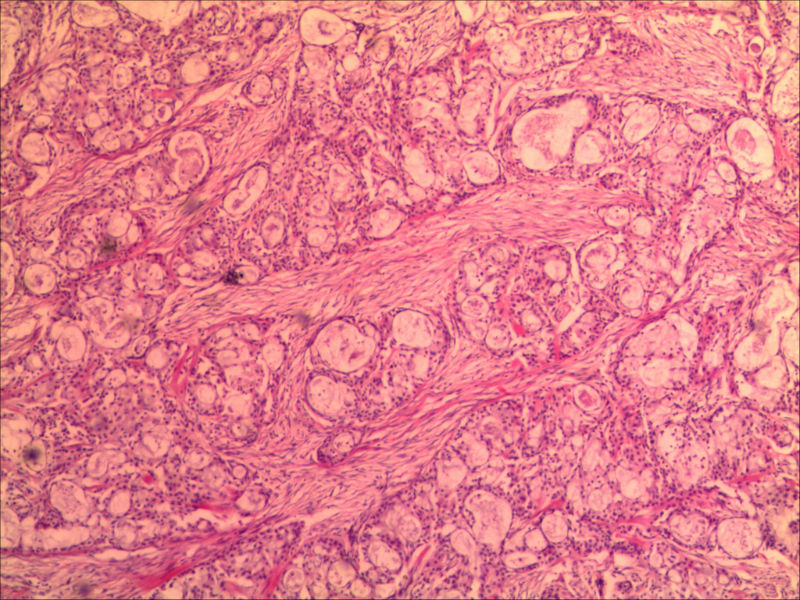

右下颌肿物女26岁 大家帮帮看看

肿物有完整包膜求助

下颌下腺